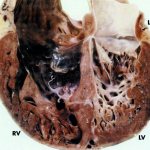

Figure 1. Blood clotting. Image: pvproductions/Depositphotos